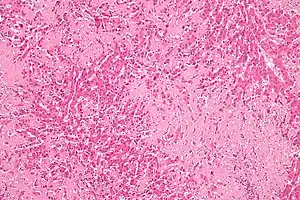

| Micrograph of liver amyloidosis, H&E stain |

Secondary systemic amyloidosis is a condition that involves the adrenal gland, liver, spleen, and kidney as a result of amyloid deposition due to a chronic disease such as Behçet's disease, ulcerative colitis, etc.[1]: 520 [2] The condition is caused by an abnormality in plasma cells.